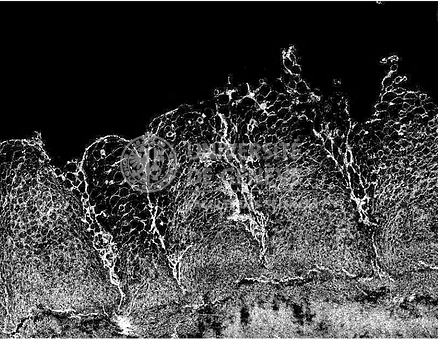

Developing methods to improve loca drug delivery to the oral cavity

• Another new research activity has been an investigation into how short duration buccal iontophoresis can be used for the local treatment of diseases in the oral cavity.

• We have developed test systems to better approximate application conditions in vivo and focused on optimizing delivery kinetics and bioavailability for mono- and poly-therapy after short duration iontophoresis.